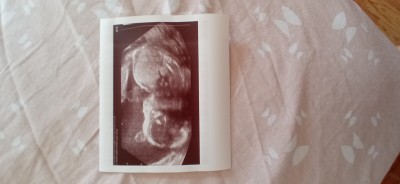

Merhabalar kızlar. Kaç haftadır isteye isteye güç bela bir fotoğraf aldım doktorda. Sürekli poz vermiyor verse vericem diyordu bu defa yine dedi annesi poz vermiyor dedi olsun hocam bir karaltı da olsa verin dedim :) bu resmi verdi.Sorum şunlar sizlere :

- 22+3 haftalık için normal görünüyor mu resim

- Bana kafası düzgün alnı açık geldi( yanılıyor muyum bilmem )  başka da bişey göremedim. Siz neler görüyorsunuz resimde yazsaniza lütfen ya çok heyecanlıyım :)

Resim unutmuştum yükledim şimdi . Baştaki başı göbeği diye yazdığım belki karıştıran olur benim gibi dedim ben doktora göbeğini gösterip burası başı mı diye sormuştum :). Ortadaki resim yan çekilmiş ekranı yan çevirip bakın ona da.

Gebelik haftası 22+4